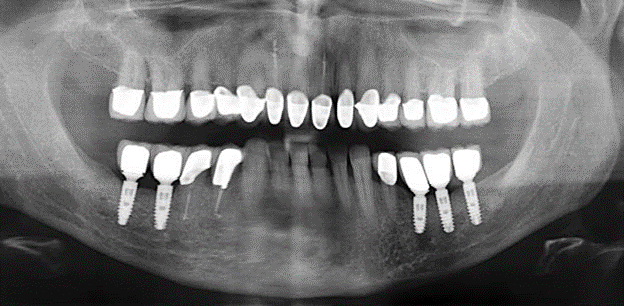

Un'assistenza standardizzata e regolare a misura di rischio nell'ambito di SPT è la chiave per il successo del trattamento clinico a lungo termine nei pazienti con situazione periodontale compromessa. Ciò è particolarmente vero per i pazienti a cui vengono applicati impianti dopo il trattamento parodontale completato con successo (Fig. 11a e b).

Un paziente di 52 anni si è presentato nella nostra clinica per la prima volta nel 2004 a seguito della perdita dei denti nel terzo quadrante, esprimendo il desiderio di un nuovo restauro protesico. La diagnostica parodontale e radiologica ha rivelato la necessità di un ampio trattamento parodontologico. Inoltre, ai denti 48, 28 e 27 è stata attribuita una prognosi molto scarsa e sono stati successivamente estratti (Fig. 1). A seguito del trattamento periodontologico sistematico completato con successo, è stato inserito una protesi dentale fissa con l'inserimento di cinque impianti nelle regioni dentali 35, 36, 37, 46 e 47. Il trattamento protesico dei denti naturali è stato effettuato con corone rivestite in ceramica di biossido di zirconio; gli impianti two-piece composti da abutment singoli in biossido di zirconio e corone similmente rivestite in ceramica di biossido di zirconio (base Cercon colorata, Dentsply Sirona Lab). L'inserimento definitivo del restauro protesico è avvenuto nel 2005.

Il controllo decennale non ha rivelato alcuna indicazione dell'avanzamento della perdita di attaccamento clinico o della perdita di sostanza ossea perimplantare (Fig. 3).